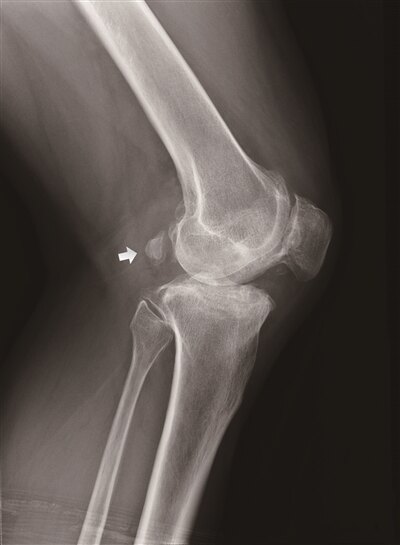

腓腸豆骨是在膝關節X片側位片上在膝關節後方的1-2個邊緣光滑、形狀不一、蠶豆大小的小籽骨,呈圓形或橢圓形,一般大小如黃豆或蠶豆,可位於股骨內外側髁表面任何位置,且股骨內外側髁又是腓腸肌內外側頭的起始附著點,故得此名。發生率在30%至50%左右,其中女性多於男性,外側多於內側。

腓腸豆綜合徵是腓腸豆骨刺激周圍組織引起的臨床疾病,其臨床表現為:膝關節後外側間歇疼痛,在伸膝、深蹲、上下樓梯時疼痛加重,腓腸豆骨所在區域有侷限性的壓痛,腫脹。有的因為刺激到腓總神經出現小腿外側的麻木不適。